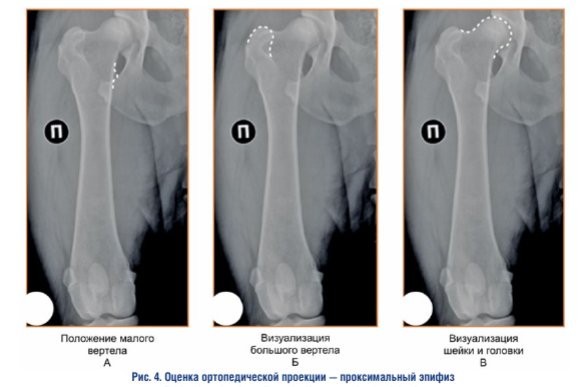

Оценка ортопедической проекции — проксимальный эпифиз. При интерпретации правильной ориентации проксимального эпифиза бедренной кости во фронтальной плоскости необходимо учитывать усредненную совокупность признаков, каждый из которых по отдельности не является абсолютным критерием адекватности проекции 1.

Положение малого вертела. Малый вертел должен хорошо визуализироваться, иметь четкие контуры и точные границы, его медиальный край должен уверенно, но не избыточно выступать за границы медиального кортикального слоя бедренной кости.

Визуализация большого вертела. Большой вертел должен хорошо визуализироваться, иметь четкие контуры и точные границы.

Визуализация шейки и головки. Головка и шейка должны хорошо визуализироваться, иметь четкие контуры и точные границы.

При наличии выраженного остеоартрита тазобедренного сустава границы шейки и головки бедренной кости могут быть значительно изменены, что может затруднять нормальное определение их контуров и точных границ.